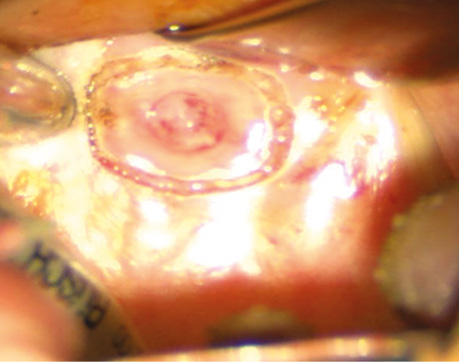

Пацієнт С., 56 років. Діагностовано плоскоклітинну карциному передньої піднебінної дужки з поширенням на корінь язика T2N0M0. Проведено трансоральну CO₂-лазерну резекцію бічної стінки ротоглотки та кореня язика доступом через сформоване «вікно» в ділянці дна ротової порожнини. На рис. 3–6 наведено етапи хірургічного втручання.

Рис. 6. Вид операційної рани після трансоральної CO₂-лазерної резекції бічної стінки ротової частини глотки та кореня язика